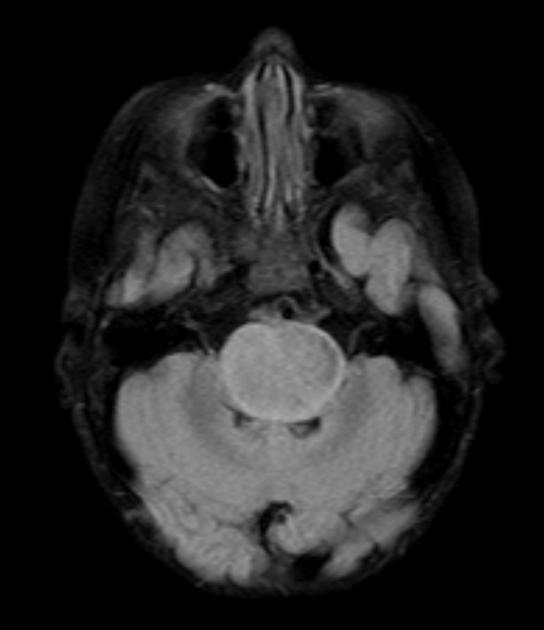

They appear on MRI T2 or FLAIR. The presence of ring enhancement suggests high grade disease. See Radiopedia for more images of diffuse pontine gliomas.

T2

FLAIR